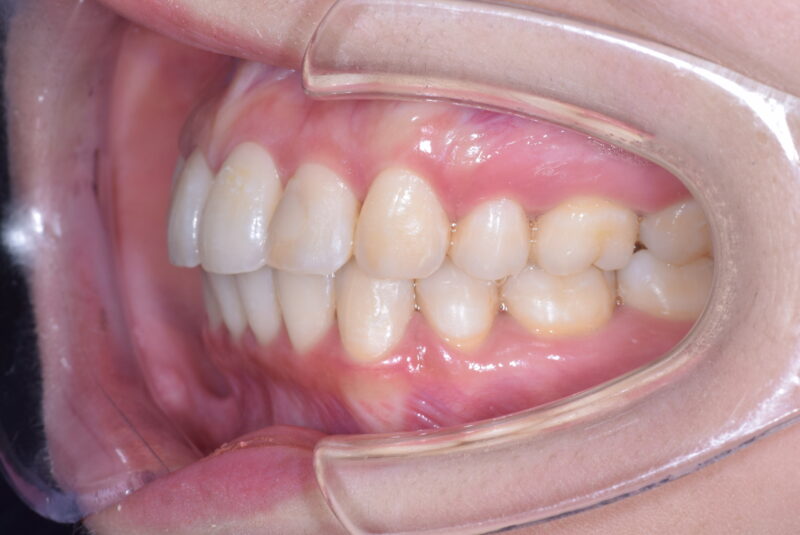

症例27 重度叢生症例

・治療前

・治療中

・治療後

①主訴 歯ならびが悪い

②診断名 前歯部叢生 Angle Cl. I

③年齢 20代女性

④治療に用いた主な装置 上顎:表側の装置 下顎:表側の装置

⑤抜歯部位 上顎:左右第一小臼歯 下顎:左右第一小臼歯

⑥治療期間 1年5か月

⑦治療費 850,000円

⑧リスク副作用 痛み・治療後の後戻り・歯根吸収・歯髄壊死・歯肉退縮などが一般的なリスクと副作用です。